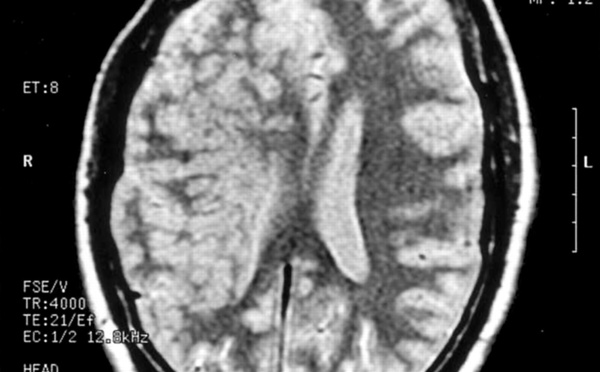

El gen que protege contra el cáncer de mama controla también el desarrollo del cerebro - 18/03/2014

El gen BRCA1, que tiene funciones protectoras contra el cáncer de mama y de ovario, tiene también un papel importante en el desarrollo del cerebro embrionario y en el control del tamaño de este órgano en adultos. Mediante experimentos con ratones, investigadores estadounidenses han demostrado que la falta de este gen provoca muerte celular y pérdida de tejido cerebral.